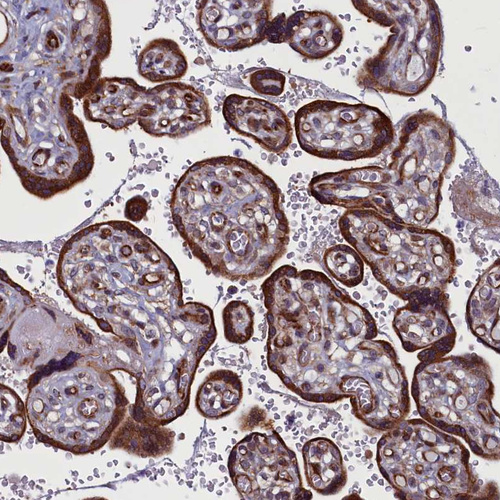

Immunohistochemical staining of human testis shows strong cytoplasmic positivity in spermatogonia.